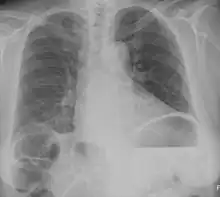

Chest X-ray showing obvious Chilaiditi's sign, or presence of gas in the right colic angle between the liver and right hemidiaphragm. | |

Chilaiditi syndrome is a rare condition when pain occurs due to transposition of a loop of large intestine (usually transverse colon) in between the diaphragm and the liver, visible on plain abdominal X-ray or chest X-ray.[1]

Normally this causes no symptoms, and this is called Chilaiditi's sign. The sign can be permanently present, or sporadically. This anatomical variant is sometimes mistaken for the more serious condition of having air under the diaphragm (pneumoperitoneum) which is usually an indication of bowel perforation, possibly leading to surgical interventions.